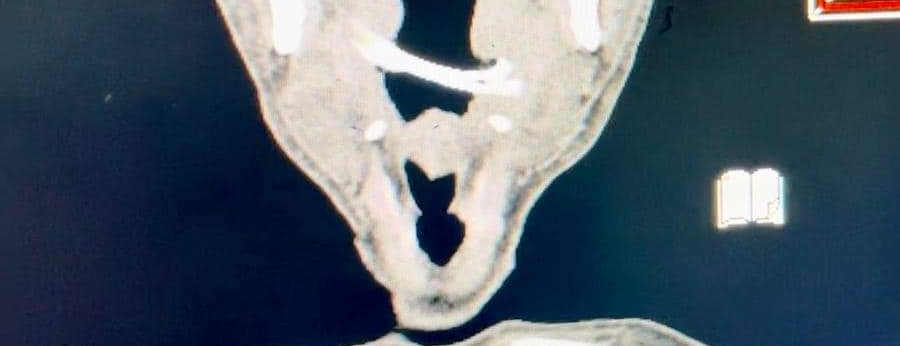

العظمة التي تم استخراجها من المريض

نجح فريق طبي متخصص بكلية الطب بجامعة الوادي الجديد، من استخراج عظمة انحشرت في بلعوم أحد الأشخاص لمدة أسبوعين بطول 6 سم.

وقال بيان أصدرته كلية الطب بجامعة الوادي الجديد، إنه تم استخراج عظمة طولها أكثر من 6 سم من البلعوم الحنجري باستخدام المنظار وبدون فتح خارجي وتحت تأثير مخدر عام، لمواطن حضر إلى استقبال مستشفى الخارجة ويبلغ من العمر 57 عاما، يعاني من صعوبة في البلع وألم شديد وغير مستجيب للعلاج لمدة أسبوعين.